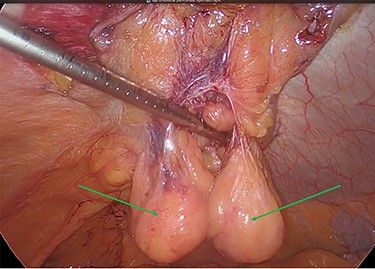

The viable omentum was reduced into the peritoneal cavity. Two lipomas were then observed attached to the parietal peritoneum (Figs 3 and 4). The lipomas were also reduced into the peritoneal cavity from within the hernia sac. Each one was 2 cm in diameter based on laparoscopic visualization using the 1 cm markings on a suction irrigation device.

Reduction of the first peritoneal lipoma (green arrow) into the peritoneal cavity.

The two peritoneal lipomas (green arrows) and the visible umbilical hernia neck (blue circle). Intracorporeal suturing of the hernia neck (green arrow) and closure of the hernial defect.